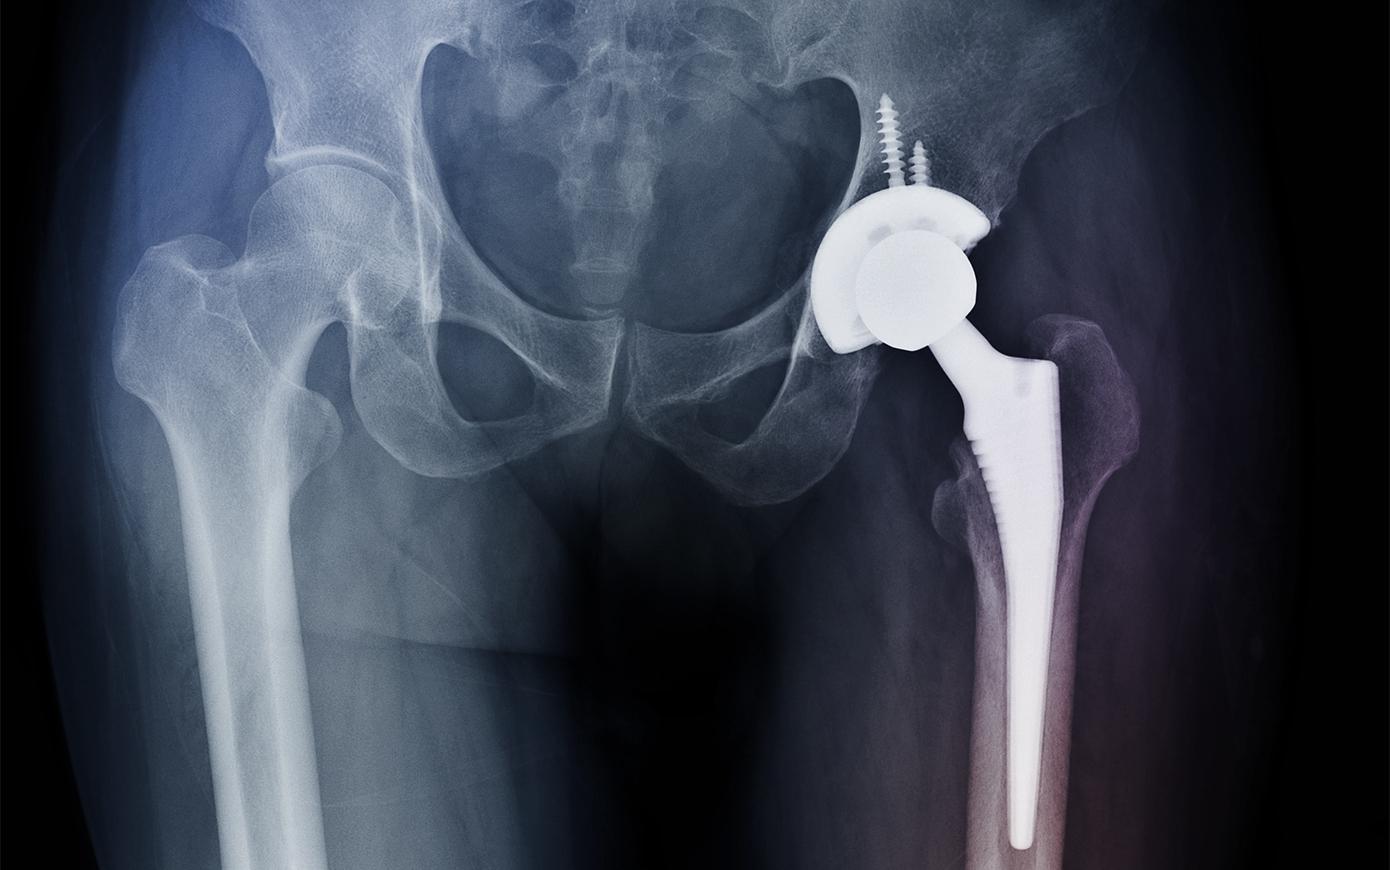

Таз делят на два отдела: верхний, более широкий — большой таз (лат . pelvis major), и нижний, более узкий — малый таз (лат . pelvis minor), разделённые пограничной линией, проходящей через мыс крестца, дугообразные линии подвздошных . . .

таз — (тазовый пояс), у человека - часть скелета, осуществляющая связь нижних конечностей с туловищем . Служит опорой конечностей и поддерживает внутренние органы . Образован парными . . .